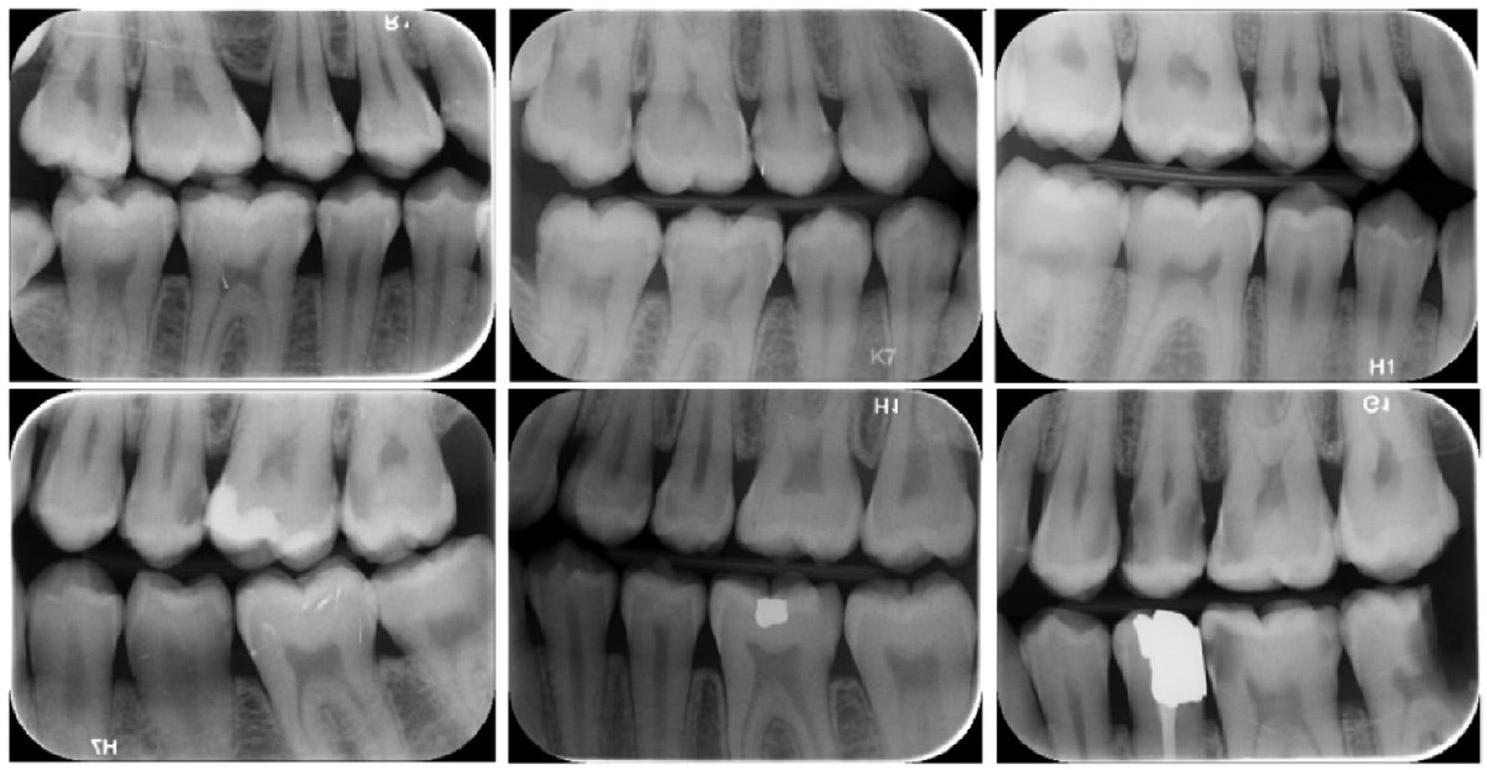

Image evaluation and data labeling

to Federation Dentaire International (FDI) tooth notation system (16-17-18-26-27-28-36-37-38-46-47-48 (molars), 14-15-24-25-34-35-44-45 (premolars) and 13-23-33-43 (canines)). Also, caries lesions labeled as decay in digital bitewing images. While in the data labeling procedure,

annotators reviewed the bitewing images at the same time and as a result of the agreement, labeling was processed (Fig. 3).